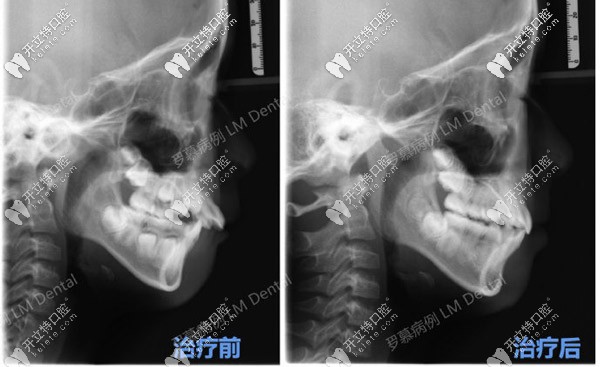

CT可以明顯看到羅慕干預(yù)后的效果

CT可以明顯看到羅慕干預(yù)后的效果▲

診斷結(jié)果:骨性Ⅱ類、安氏Ⅱ類、前牙深覆蓋Ⅲ類、深覆合Ⅰ度、上下牙弓狹窄

十歲女孩的上牙明顯前突,12個(gè)月后牙齒咬合誘導(dǎo)矯正前后發(fā)生的變化,可能會(huì)讓你更加關(guān)注寶寶的牙齒。